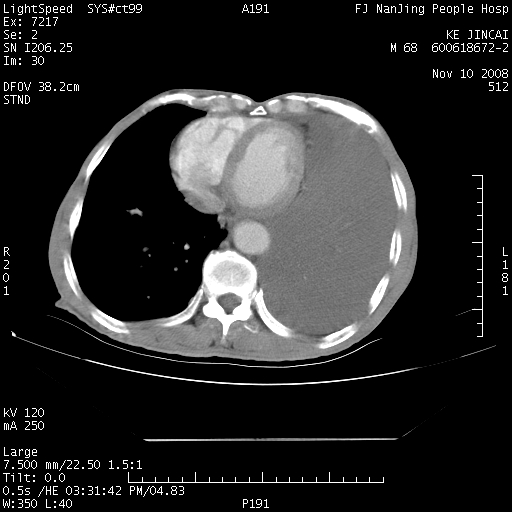

是个很有看头的病例,咋人气那么不旺?没多少人兴趣呢?这个病例几大怪:1   恶性肿瘤侵犯心肌左房怪,心肌一般不会被恶性肿瘤侵犯吧?2   左下肺均匀实变怪,内无含气,有别一般不张实变,含气肺泡完全为液体取代,而非一般不张实变的肺萎陷,冷不丁还以为是肿大的脾脏3   肿瘤本身怪,像tb肺不张4   这么有看头的病例没人气怪。呵呵。

追查病史,咳嗽,患者无发热,血象不高。据说2年前胸片检查怀疑肺ca曾行纤支镜检查,病理未见到癌细胞。无确切资料。

左肺恶性肿瘤侵犯肺动脉,左心房内瘤栓,胸膜转移。

左肺恶性肿瘤侵犯肺动脉,左心房内瘤栓,胸膜转移,少见,学习了。